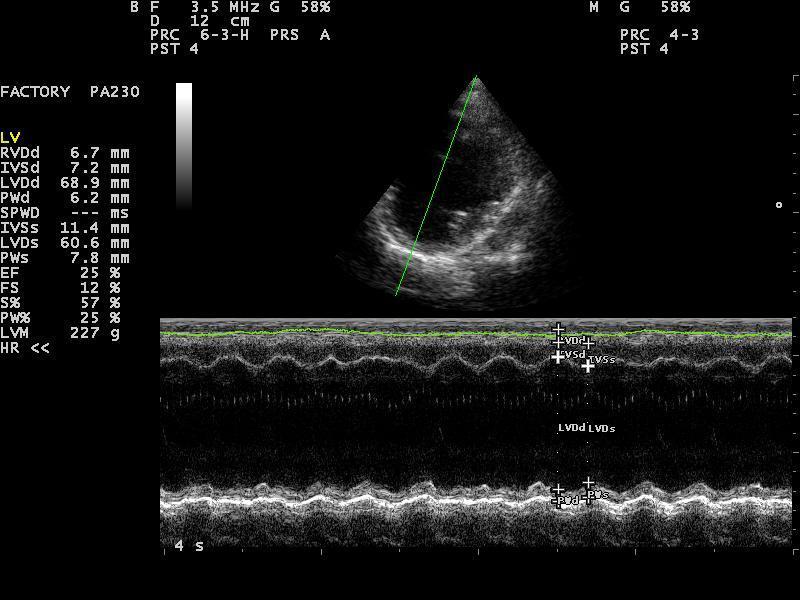

Kadar veterinar pri tem posumi na bolezen srca, je potreben celosten pregled kardiovaskularnega sistema, ki ga opravi veterinar – kardiolog. Ta večinoma obsega klinični pregled, ultrazvok srca, EKG in ob sumu na dekompenzacijo rentgen pljuč. To nam omogoči postavitev natančne diagnoze, ki je ključnega pomena za uspešnost terapije in dolgoročno prognozo.

Dilatativna kardiomiopatija in sekundarne kardiomiopatije

Pri tej okvari srca gre za primarno izgubo moči srčne mišice. Najpogosteje so prizadete večje pasme, od manjših pa nekateri španjeli. Za bolezen je značilna dolga, večinoma več let trajajoča latentna faza, v kateri je možno bolezen odkriti le z natančnim kardiološkim pregledom. V končnem stadiju bolezni pa pride tudi do dekompenzacije z zastajanjem tekočine v pljučih in trebušni votlini, motnjami srčnega ritma, izgubo telesne teže in mišične mase. Žival pri tem težko diha, se hitro utrudi, lahko občasno izgubi zavest; nekateri psi pa brez predhodnih bolezenskih znakov nenadoma poginejo. Pravočasno prepoznavanje bolezni je pomembno tako z vidika zdravljenja kakor tudi zaradi izločitve prizadetih živali iz vzreje. V večini primerov se z ustreznim zdravljenjem precej podaljša dolžina in kakovost življenja prizadetih psov; nekateri tipi kardiomiopatije pa so celo ozdravljivi.

Omenjene bolezni so le ene od tistih, s katerimi se srečujemo veterinarski kardiologi; seveda pa je srčnih obolenj še veliko več. Za uspešnost zdravljenja je največjega pomena natančna diagnoza. Te si v današnji veterinarski kardiologiji, ki v mnogih stvareh sledi humani medicini, ne moremo več predstavljati brez specialističnih preiskav. Sem sodi na prvem mestu ultrazvočna preiskava srca, ki je za postavitev diagnoze nepogrešljiva. Za celostno sliko obolenja pa večinoma potrebujemo še dodatne preiskave, kot so rentgensko slikanje pljuč, elektro kardiološka preiskava srčnega ritma, merjenje krvnega tlaka. Terapijo je nato potrebno natančno prilagoditi potrebam posameznega pacienta, saj se na zdravila ne odzovejo vsi enako. Tu je izjemnega pomena tesno sodelovanje in zaupanje med skrbnikom psa in izbranim veterinarjem – kardiologom. Le na tak način si zagotovimo optimalno kontrolo bolezni ter zadovoljstvo vseh: živali, njihovih skrbnikov ter ne nazadnje nas, kardiologov.